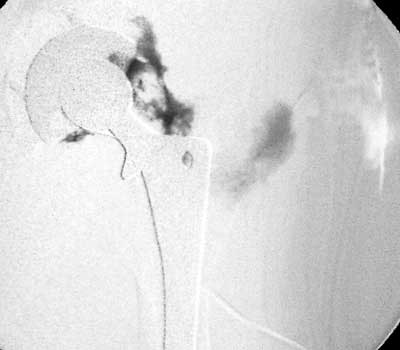

Sinus tract draining posteriorly

Arthrographic evidence of loosening—contrast enters

abnormally widened interface Gruen zone 1 and 2

Arthrographic evidence of cup loosening—contrast enters

abnormally widened interface Gruen zone II and III